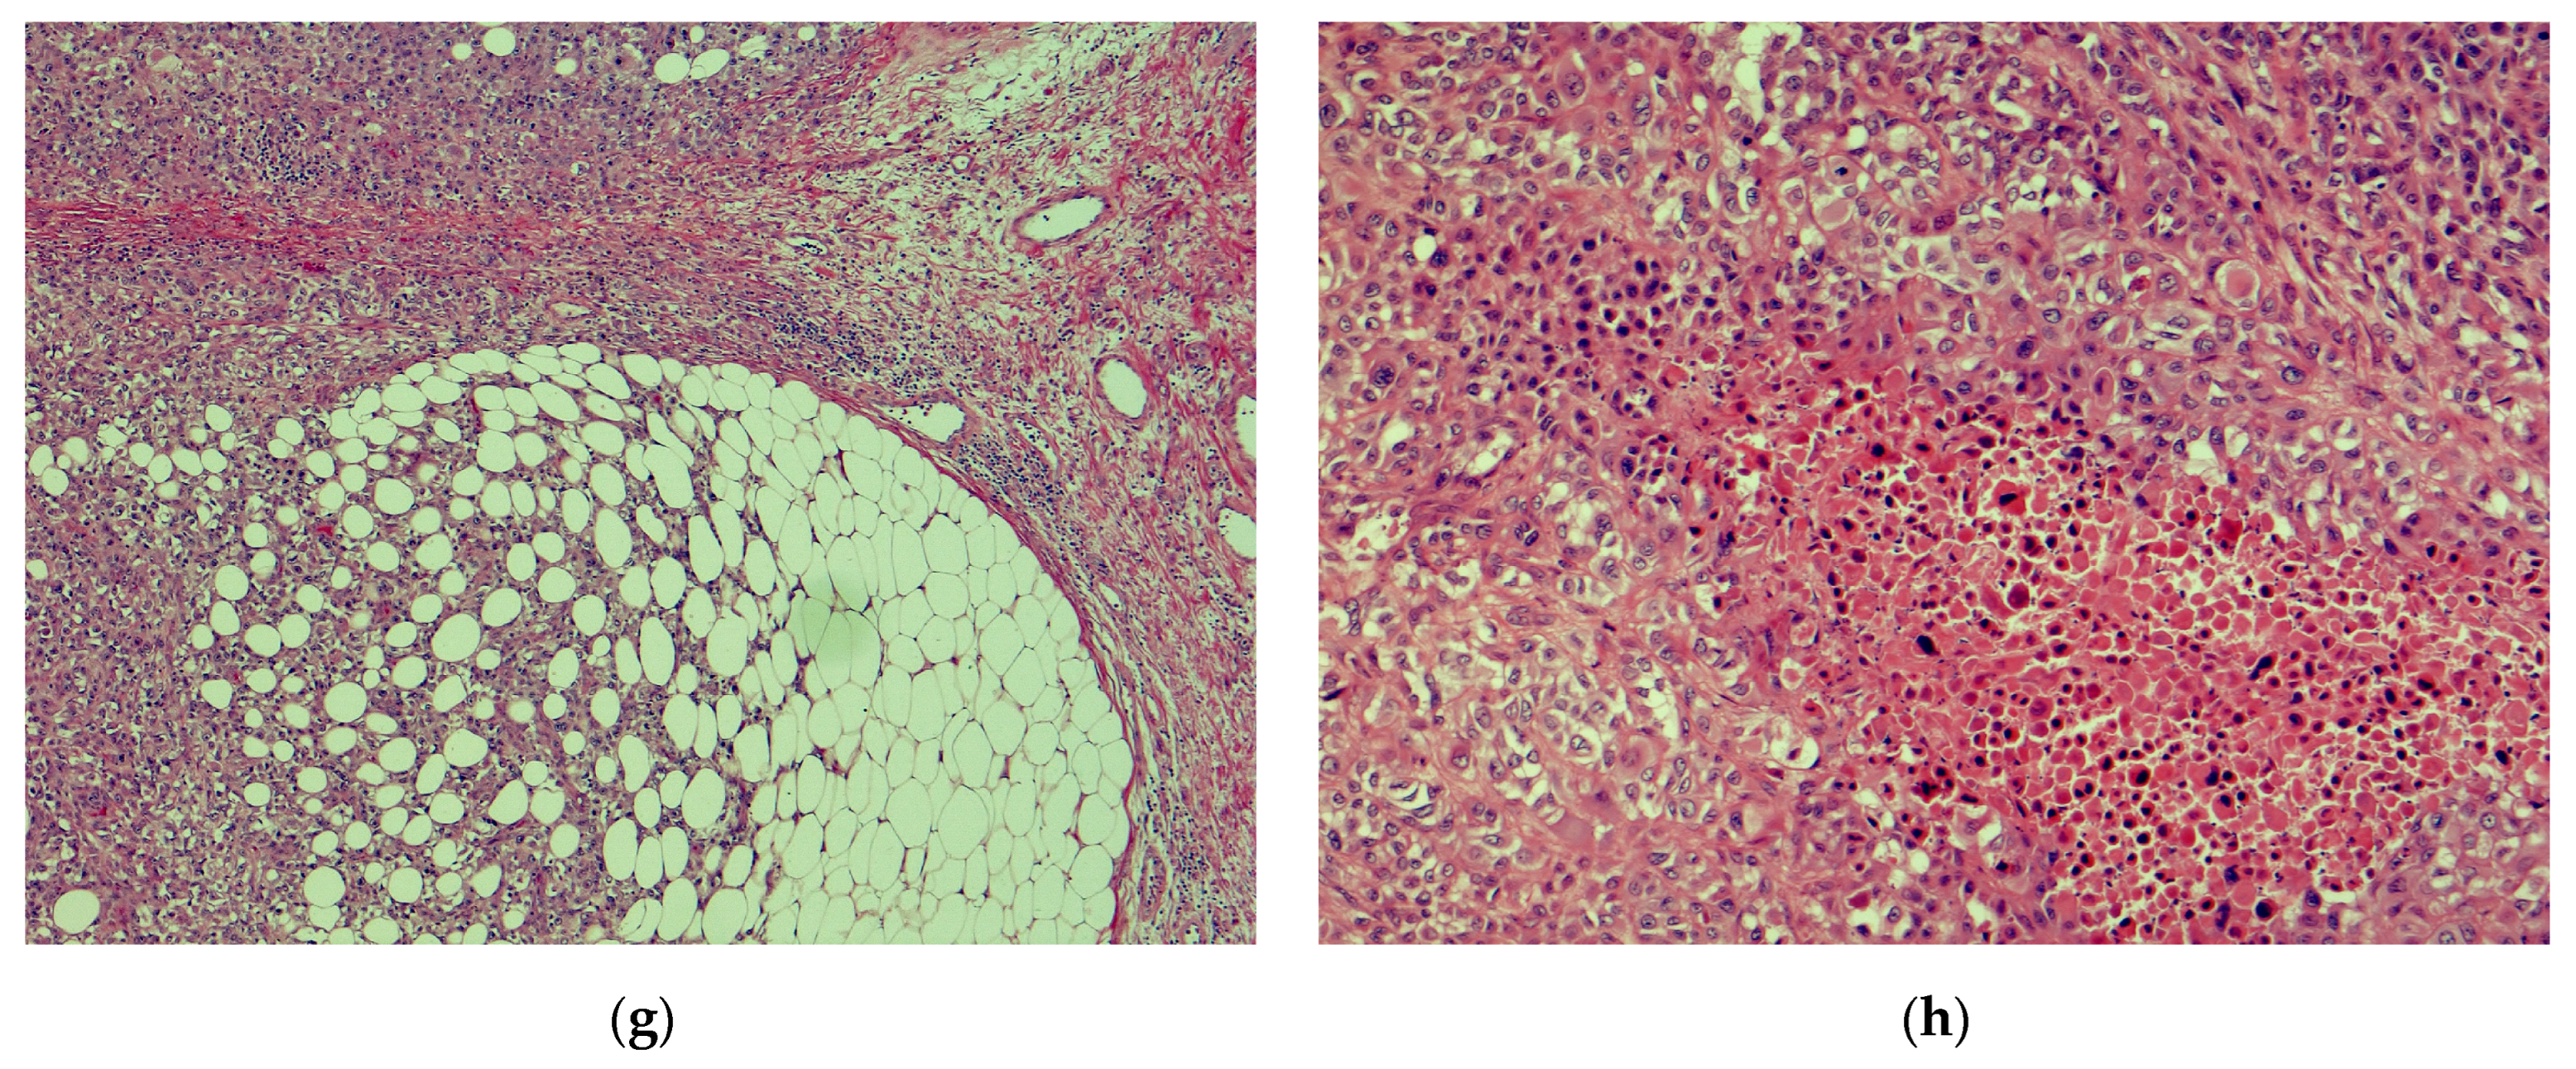

2. Distinction between AFX and PDS

4. Surgical Management of AFX and PDS

5. Histopathologic Evaluation of Debulk Specimen

6. Importance of Histopathologic Evaluation of Debulk Specimen of AFX and PDS